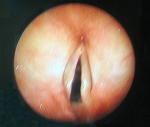

• Endoscopia respiratoria cuerda vocal izquierda con deficit en su movilizacion y apecto normal, traquea y bronquios: hiperemia e hiper-secresión bronquial, claras, no se observaron lesiones endobronquiales de aspecto neoplasico, carina del lóbulo superior izquierdo normal, arquitectura bronquial en general normal. Citologias del lavado y cepillado: inflamatorio

Laringoscopia

Broncoscopia

Laringoscopia: parexia cuerda vocal izquierda. Broncoscopia: carina del lobulo superior izquierdo